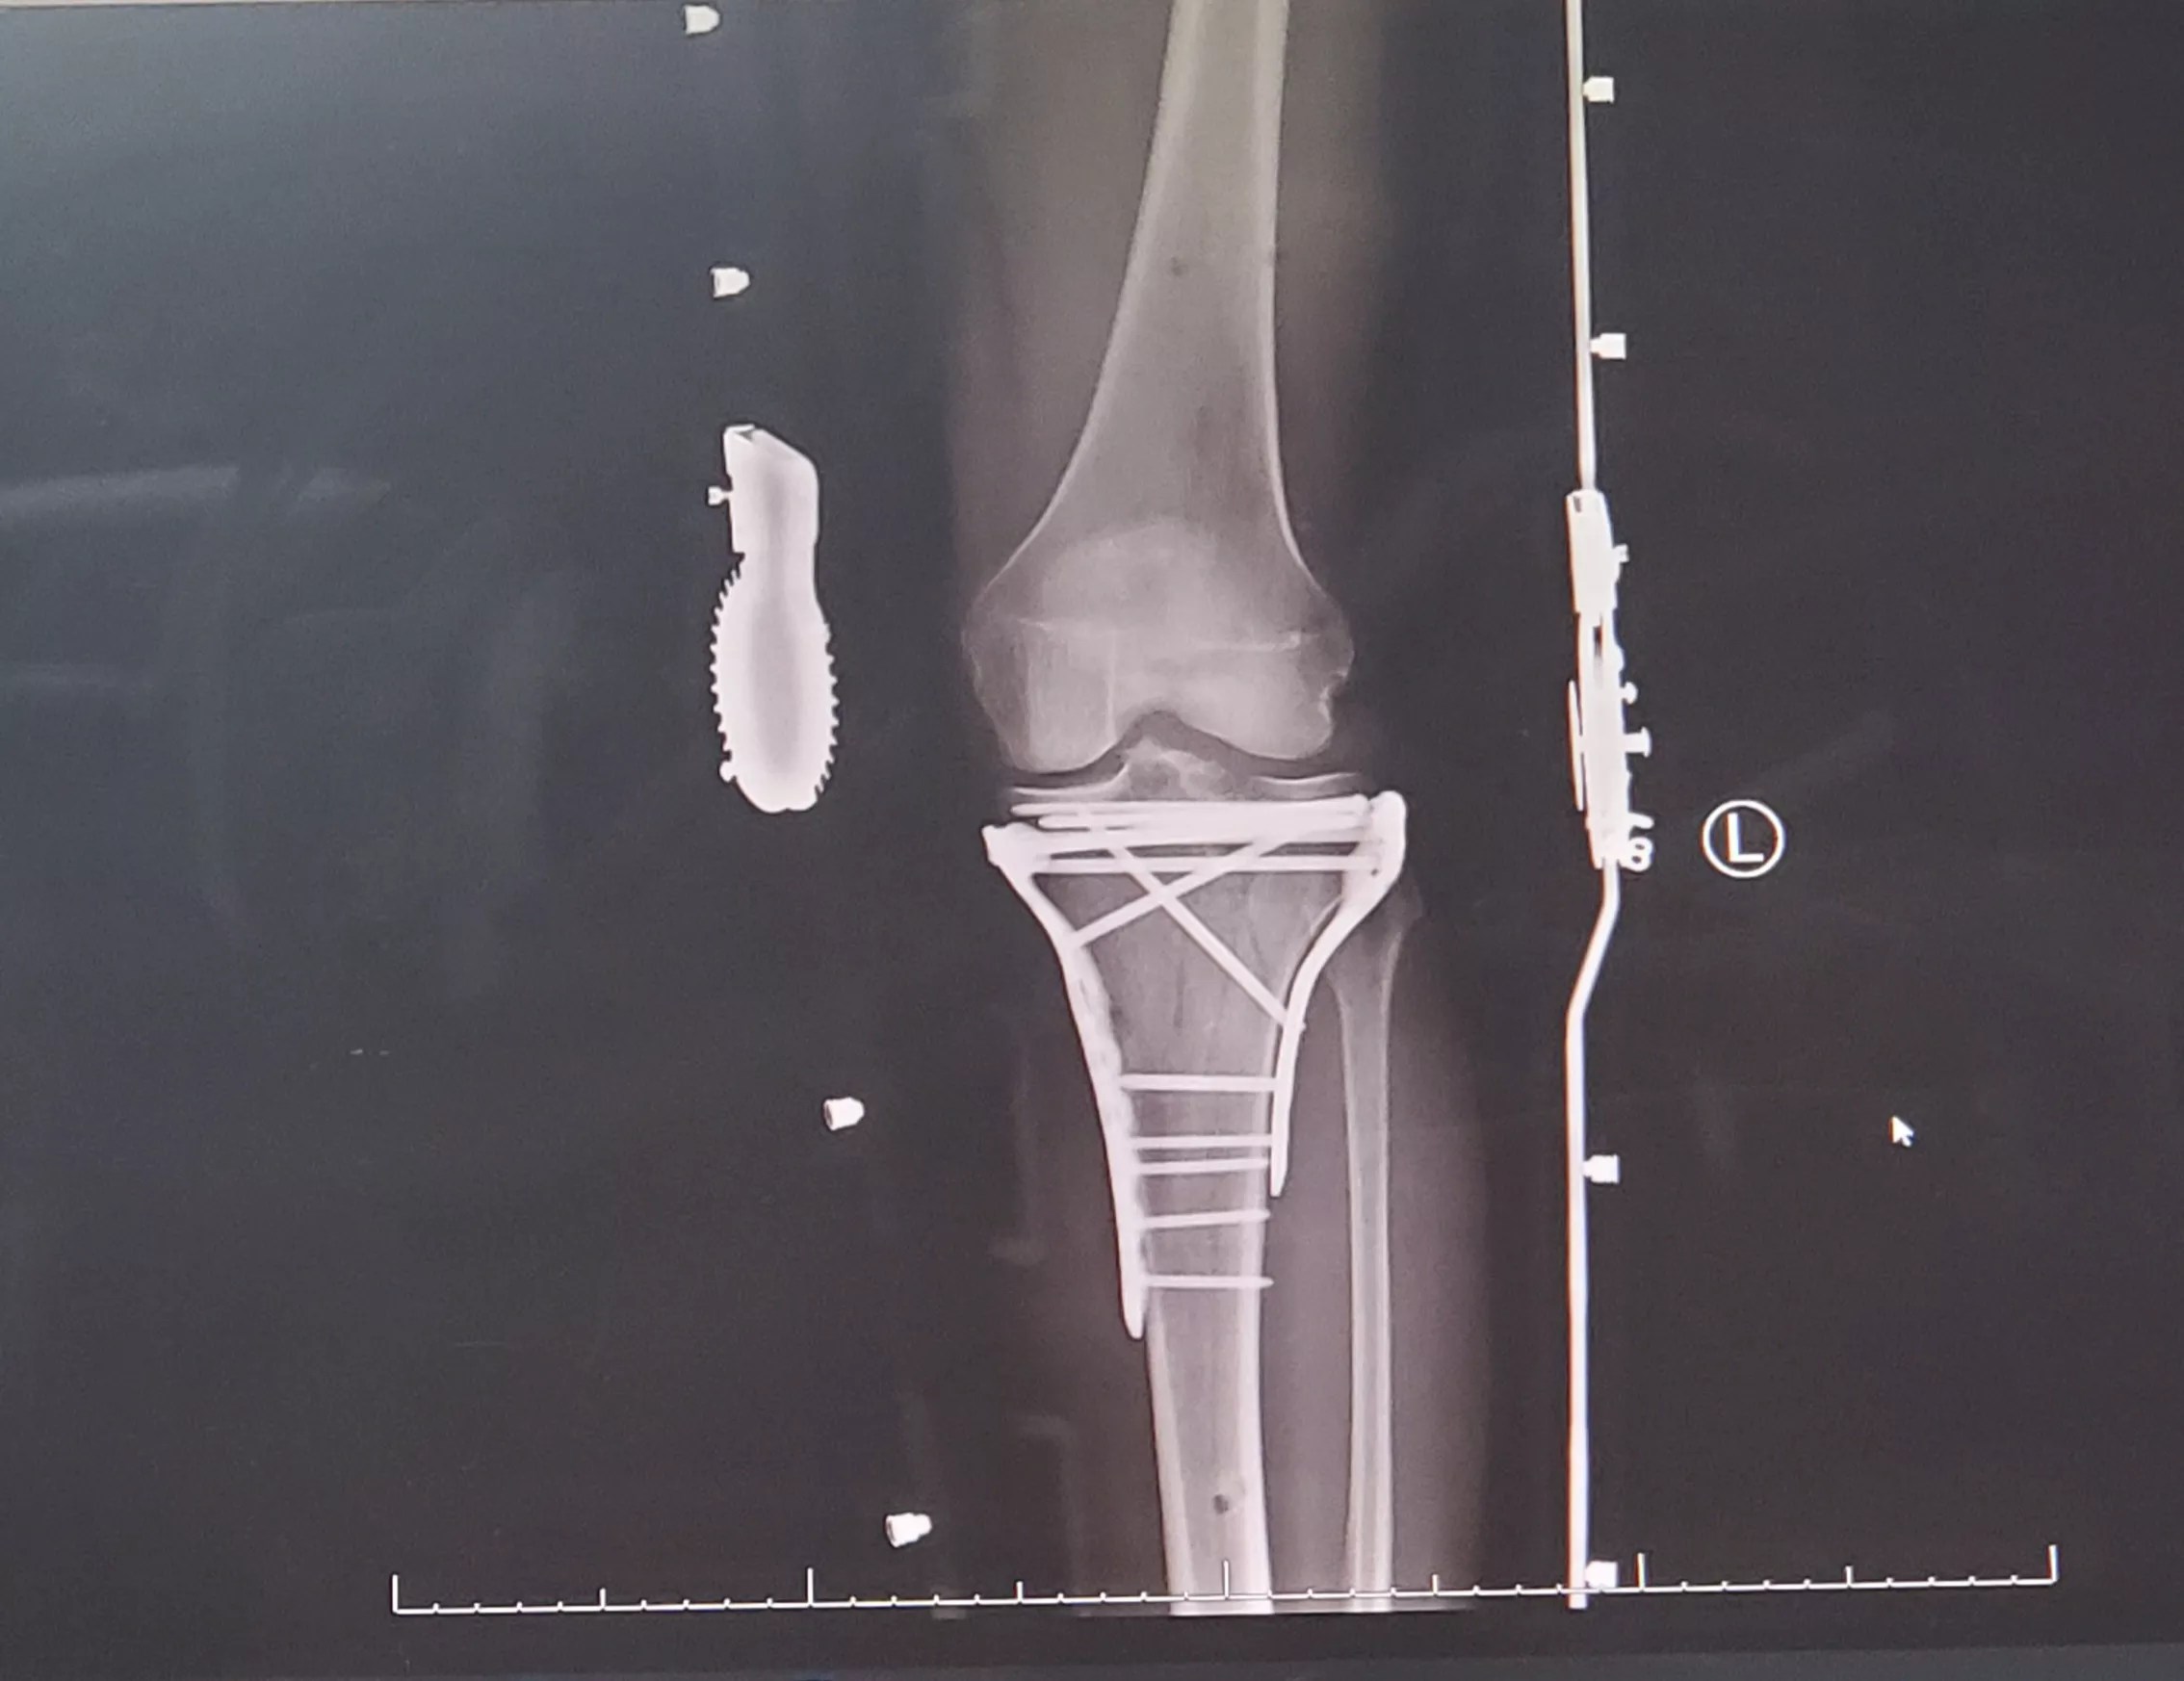

As it turned out, Penalta had fractured his tibial plateau, the flat portion at the top of the tibia where it meets the femur. The following morning, he was moved to a different hospital, where he underwent surgery to immobilize the knee joint. Three days later, after the swelling went down, a second surgery was performed to install rods and plates in his leg.

Now, 12 screws and two plates hold the tp of his tibia bone in place. Nearly three months after the accident, he still can’t place weight on his injured leg.

An X-ray image of the screws and plates in Anthony Penta’s leg